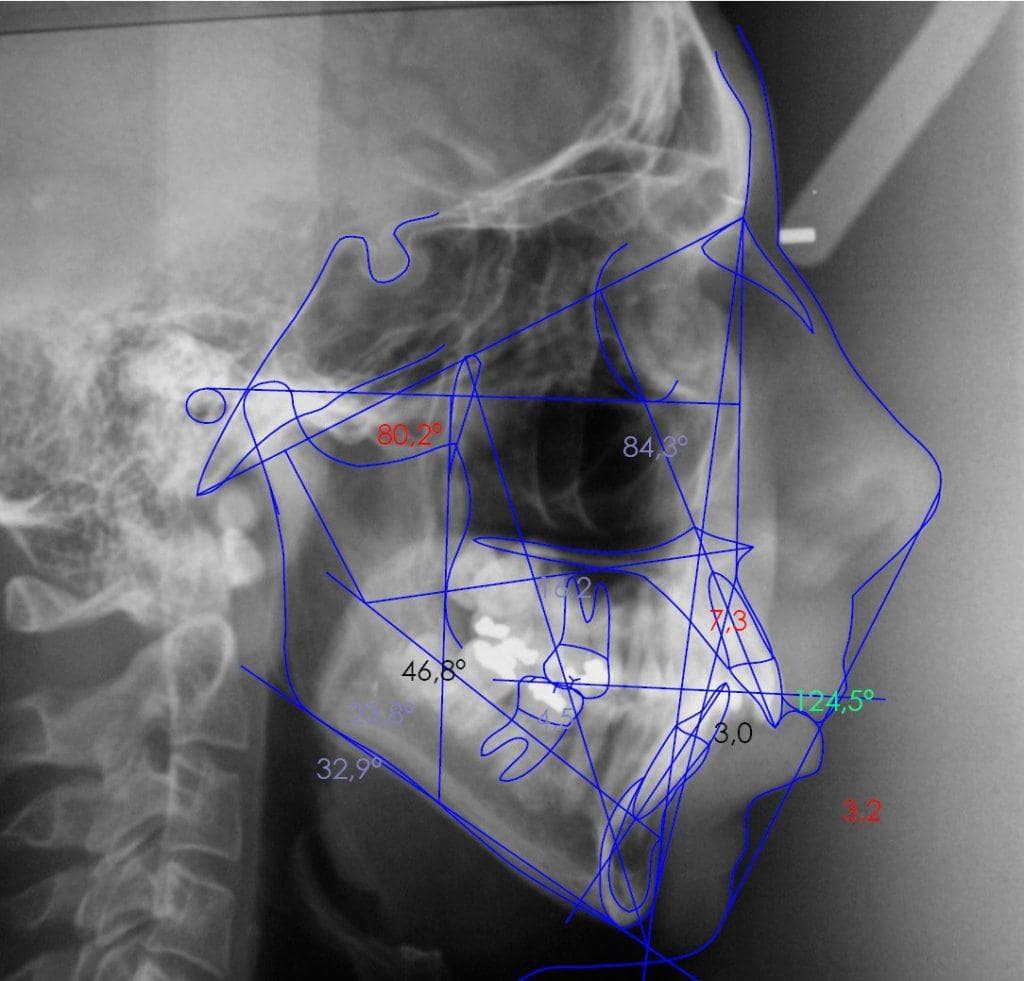

Cefalometría

La cefalometría permite obtener medidas del cráneo a partir de radiografías para establecer los puntos anatómicos más significativos y medir las distancias y relaciones entre unos y otros.

la cefalometría es un procedimiento diagnóstico fundamental antes de iniciar cualquier tratamiento ortodóncico, ya que permite determinar las anomalías morfológicas, de colocación y de crecimiento de los dientes, para así establecer el objetivo del tratamiento y poder realizar el adecuado seguimiento del mismo.